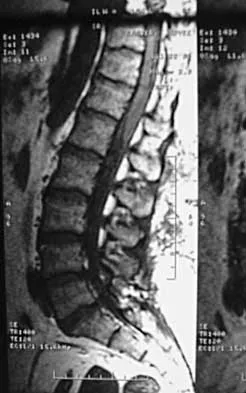

A 44-year-old woman has had lower extremity dysesthesias, urinary incontinence, and has been unable to walk for the past 2 days. She reports no pain or history of trauma. She notes that 3 weeks ago she missed work for 2 days because of back pain, but it resolved with rest. Examination shows decreased or absent sensation below the knees, no motor function below the knees, and decreased rectal tone. Catheterization results in a postvoid residual of 2,000 mL. Plain radiographs and MRI scans without contrast are shown in Figures 1a through 1d. What is the next most appropriate step in management?

Explanation

The patient has had a clear and sudden onset of a profound neurologic deficit. The radiographic studies suggest a lesion in the conus medullaris that appears to be intradural and intramedullary. MRI, with and without contrast, will best evaluate this mass further. The addition of gadolinium allows further evaluation of vascularity and the extent of the lesion. Eichler ME, Dacey RG: Intramedullary spinal cord tumors, in Bridwell KH, Dewald RL (eds): The Textbook of Spine Surgery, ed 2. Philadelphia, PA, Lippincott-Raven, 1997, vol 2, pp 2089-2116.